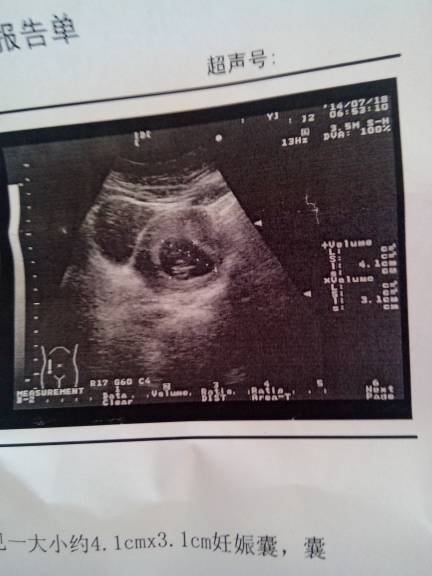

想知道自己怀的男孩女孩??谁可以看懂??? 想知道自己怀的男孩女孩??谁可以看懂??? 点击展开 銠厷ωǒ愛妳 2014-07-18 11:13 为您推荐: 其他回答 你所提示的检查结果是看不出男女的, 要顺其自然,男女一样。现在主要是增加全面的营养,保持良好的心情,合理的饮食,多吃瓜果和蔬菜,粗细搭配,安心养胎。定期孕检的。 hbwxsxl 2014-07-18 11:17 相关问题 谁弄看懂是男孩女孩呀 86年11月25号怀上的,有谁知道怎么算男孩女孩?